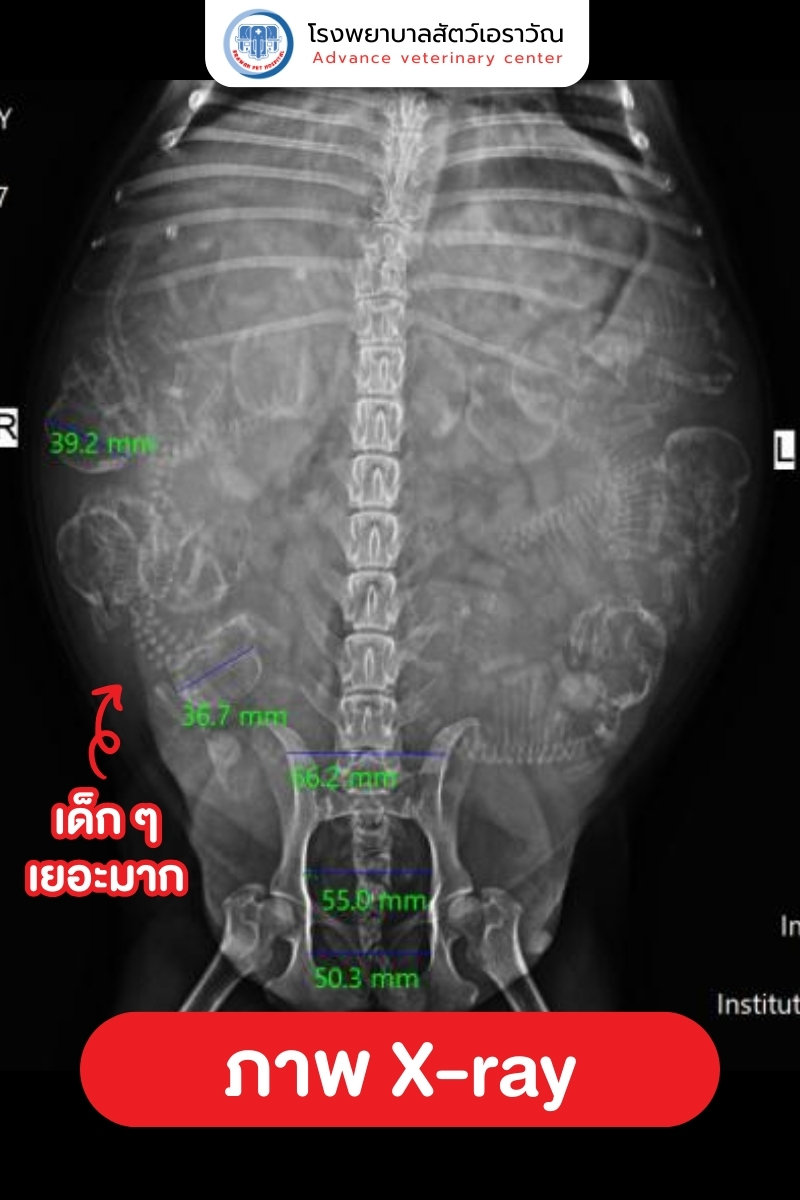

เมื่อแม่สุนัขถูกนำส่งถึงโรงพยาบาล ทีมสัตวแพทย์ได้ทำการตรวจทันที และพบว่า

- ตรวจสภาพแม่สุนัขและลูกในท้อง